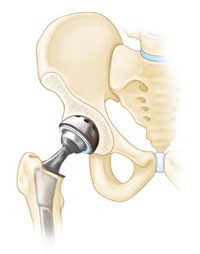

If osteonecrosis has advanced to femoral head collapse, the most successful treatment is total hip replacement. This procedure involves replacing the damaged cartilage and bone with artificial implants.

Total hip replacement is successful in relieving pain and restoring function in 90 to 95 percent of patients. It is considered one of the most successful operations in all of medicine.

When osteonecrosis is diagnosed after collapse of the bone, core decompression is not usually successful in preventing further collapse. In this situation, the patient is best treated with a total hip replacement, which relieves pain and restores function in 90% to 95% of patients.

In a total hip replacement, both the head of the femur and the socket are replaced with an artificial device.